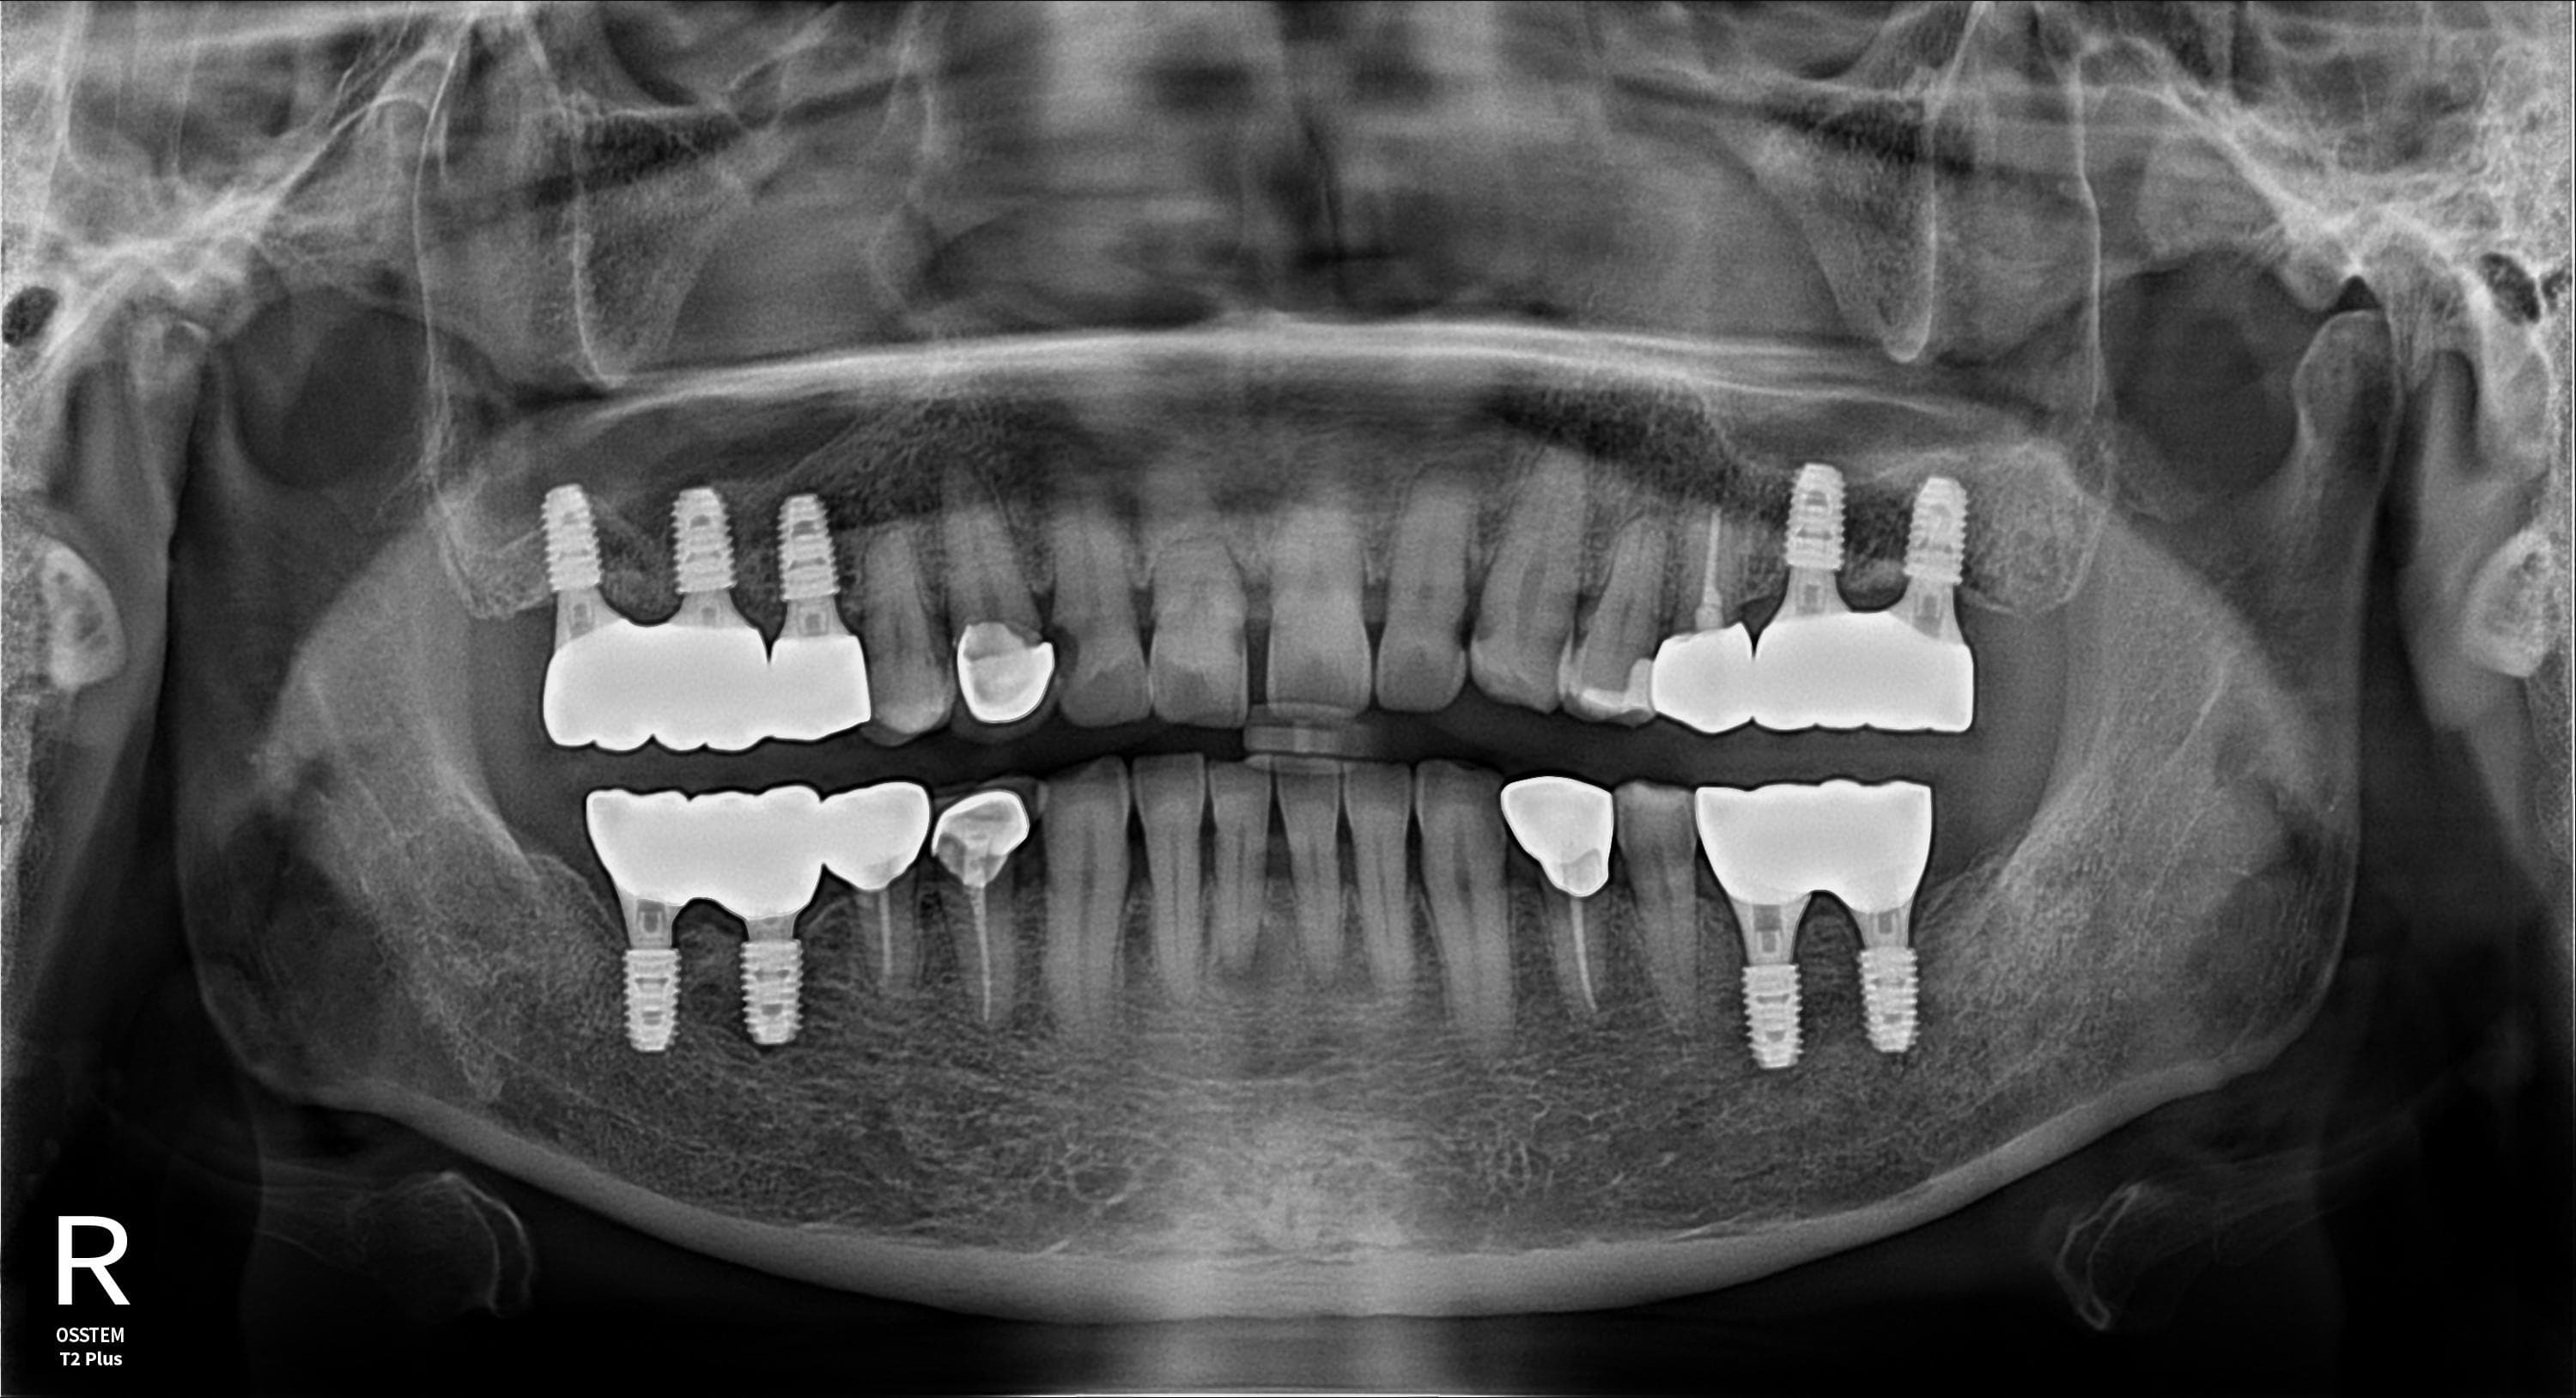

Before

임플란트 보철 · 엑스레이 · 지●● · 남성

After